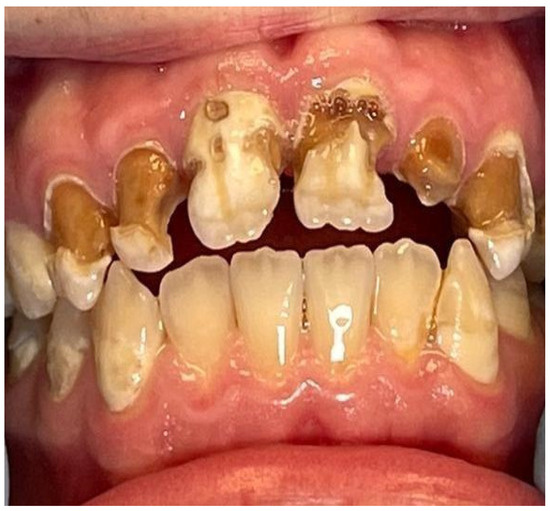

Use of Computer Digital Techniques and Modern Materials in Dental Technology in Restoration: A Caries-Damaged Smile in a Teenage Patient

2. Case Report